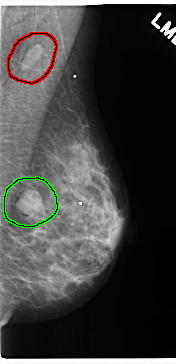

FILE: C_0212_1.LEFT_MLO.OVERLAY

TOTAL_ABNORMALITIES 2

ABNORMALITY 1

LESION_TYPE MASS SHAPE OVAL MARGINS CIRCUMSCRIBED

ASSESSMENT 5

SUBTLETY 5

PATHOLOGY MALIGNANT

TOTAL_OUTLINES 1

BOUNDARY

ABNORMALITY 2

LESION_TYPE MASS SHAPE ROUND MARGINS CIRCUMSCRIBED

ASSESSMENT 4